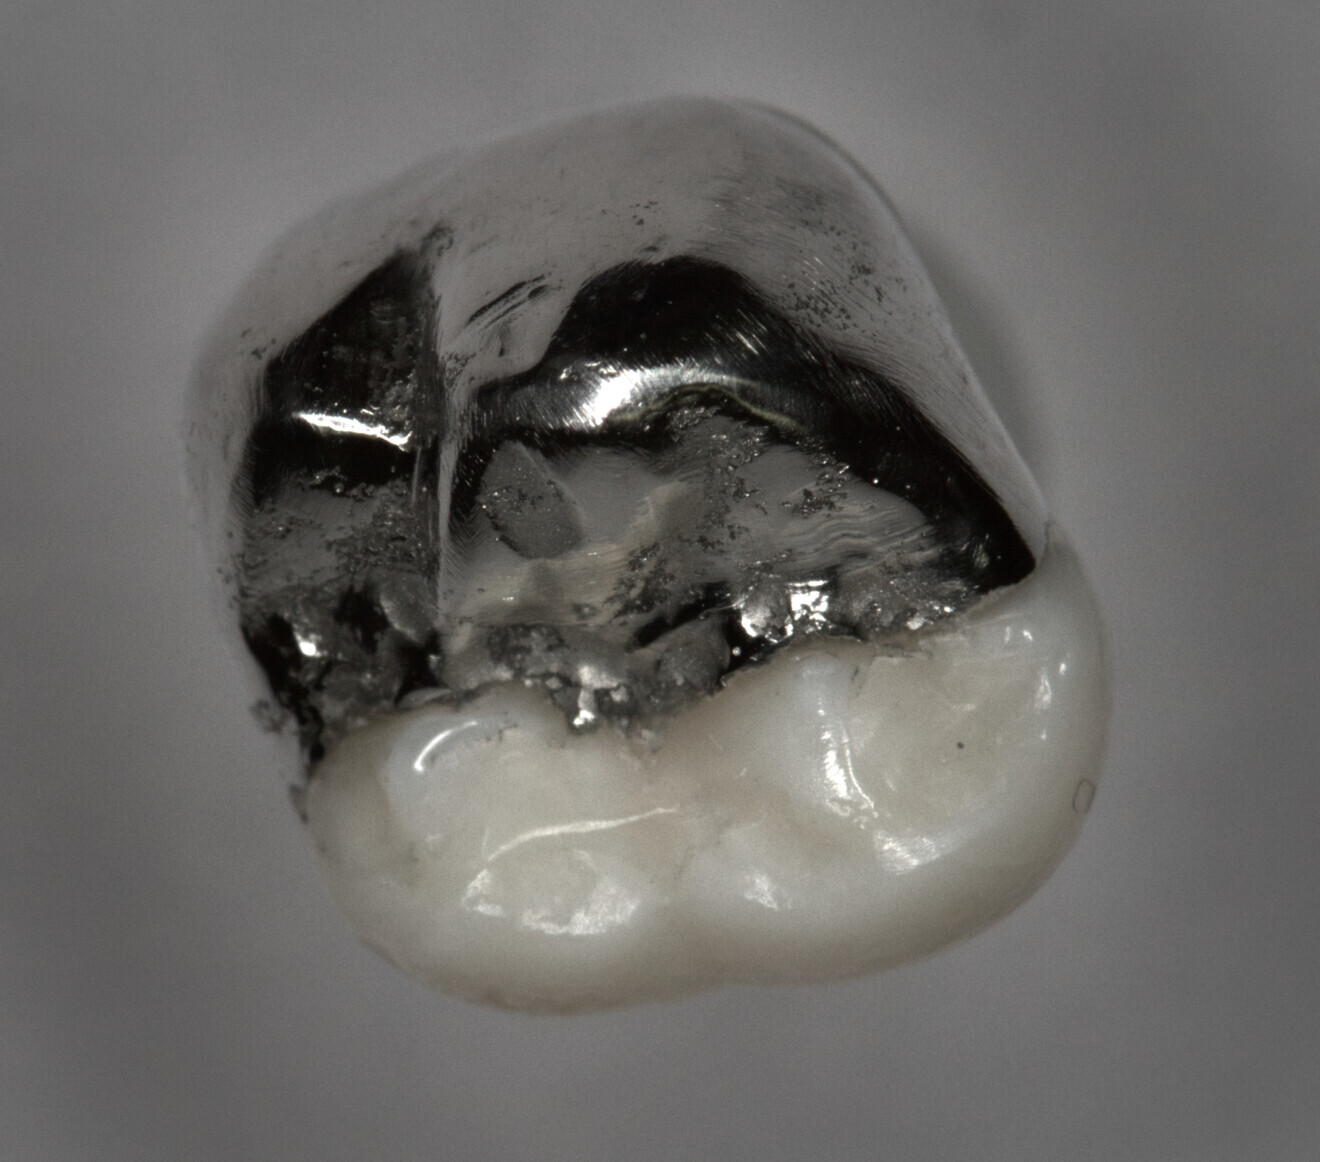

Fig. 8: Cemented onlay.

The digital scanner provided an STL file of appropriate resolution for metal additive manufacturing or 3D printing. The indirect onlays were successfully printed in cobalt–chromium with the morphology, dimensions and fit that were clinically acceptable for cementation. Cementation was completed without issue and with suitable retention, similar to previous investigations.6 The marginal adaptation was generally acceptable, except for one area, owing to an open margin. The surface finish was generally acceptable, but could be improved in some places, especially on the occlusal surface.